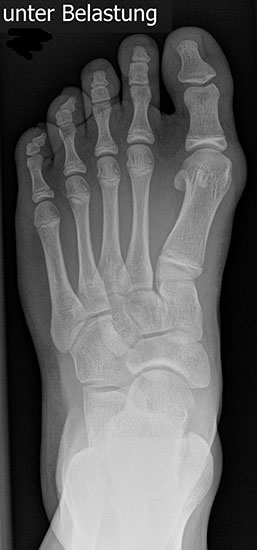

Bei einem juvenilen Hallux valgus handelt es sich um eine schon im Kindes – oder Adoleszentenalter 1 bestehende Valgusdeviation der großen Zehe bei Spreizfuß mit vergrößertem Intermetatarsalwinkel I / II aufgrund einer Adductionsstelllung des Metatarsale I – Metatarsaus primus varus.

Im Gegensatz zum Hallux valgus des Erwachsenen ist die Valgusabweichung der großen Zehe meist geringer ausgeprägt als bei Erwachsenen, der Intermetatarsalwinkel oft stark vergrößert. Die Angaben ab wann der Intermetatarsalwinkel als vergrößert gilt schwanken zwischen > 9° 2 und >14°3. Das Ausmaß der Beschwerden korrelieren nicht mit dem Auftreten und dem Schweregrad der Deformität (Zollinger 1990, Zollinger 1993). Begünstigend wirkt eine Schrägstellung des ersten Tarsometatasalgelenkes (Hefti 1998) und eine Hypermobilität dieses Gelenkes 2 in Kombination mit einer Bindegewebsschwäche. Häufig liegt eine positive Familienanamnese vor. In einer Untersuchung von Coughlin fand sich eine Vererbung über die mütterliche Linie in 72%, ein milder bis stark ausgeprägter Knick-Senkfuß in 17% (das entspricht der Quote von Knick-Senkfüßen in der Normalbevöl­kerung) aber in 22% ein Pes adductus, das ist wesentlich mehr als in der Normalbevölkerung zu erwarten wäre 4. Auch für Hefti (1998) gilt der Pes adductus als Komponente des Sichelfußes als begünstigend. Zur Inzidenz des Hallux valgus juvenilis finden sich je nach Autor verschiedene Angaben. Nach Auswertung von Schuluntersuchungen liegt die Häufigkeit zwischen 1,6 % bis 17% 56. Häufig tritt die Fehlstellung doppelseitig auf. Der Anteil der betroffenen Mädchen liegt 4-5x höher als bei Jungen (Lamprecht 2015).

Röntgen

Standard ist die belastete Röntgenaufnahme des Fußes dorso-plantar und seitlich. Günstig ist eine Röhrenkippung von 10°-20°, um die Gelenke der Lisfranc-Linie einsehen zu können.

• Hallux valgus Winkel

• Hallux valgus interphalangeus Winkel

• Intermetatarsalwinkel I zu II

• Distaler Metatarsale Gelenkwinkel (PASA)

Tabelle 1: Normwerte der Winkelmaße

Intermetatarsalwinkel Hallux valgus Winkel

Normalwerte < 10° < 20°

Leichte –mittelgradige Fehlstellung 10°- 16° 20°- 40°

Schwere Fehlstellung > 16° > 40°